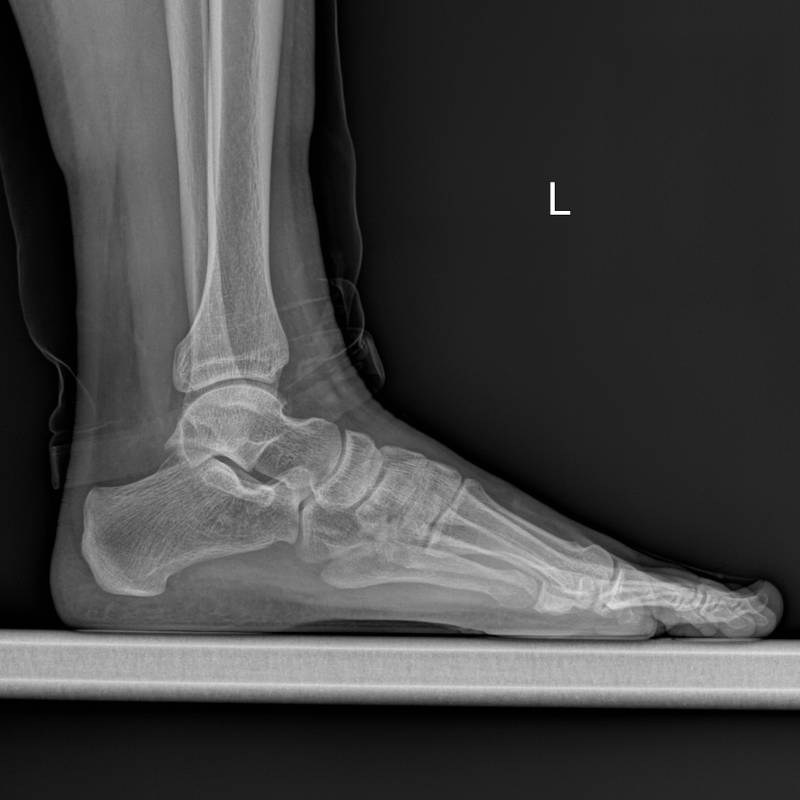

Digunakan untuk menilai struktur tulang kaki.

Pemeriksaan sinar-X pada tulang tumit untuk mengesan kecederaan.

Sinar-X untuk memeriksa kecederaan pada pergelangan kaki.